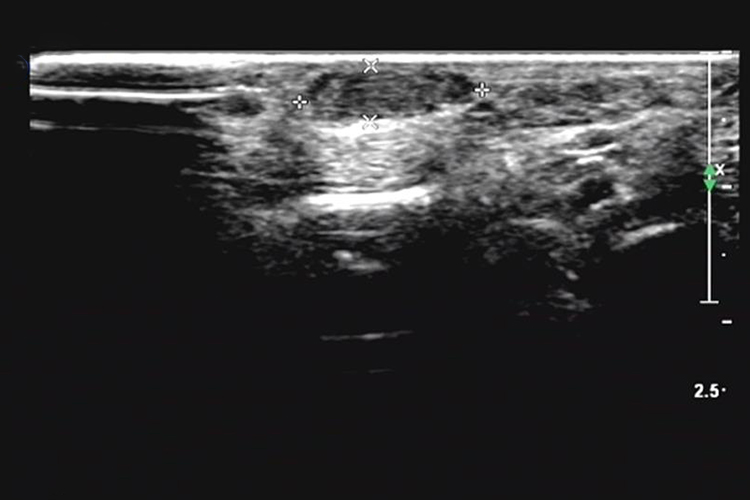

毛细血管瘤

超声检查多见低回声团块,形态欠规则,内部回声分布欠均匀,探头加压可变形。彩色多普勒血流图像示团块内部及周边可见血流信号。